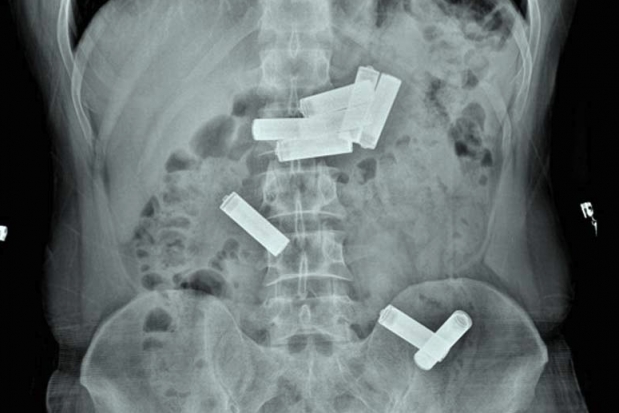

GAZİANTEP'te, işlediği bir suç nedeniyle hükümlü olarak cezaevinde kalan ve rahatsızlanınca hastaneye kaldırılan mahkumun midesinden 8 kalem pil çıktı.

Gaziantep Kapalı Cezaevi'nde kalan mahkum D.K., geçen hafta içerisinde koğuşunda rahatsızlanınca Dr. Ersin Devlet Hastanesi'ne götürüldü. Acil serviste muayenesi yapıldıktan sonra çekilen röntgende D.K.'nin midesinde 8 kalem pil olduğu saptanınca Endoskopi Servisi'ne sevk edildi. Gastroenteroloji uzmanı doktor Ahmet Yağbasan başkanlığındaki ekip, yaptığı çalışma ile D.K.'nin midesindeki pillerin birisini çıkardı. Uzmanlar, mahkumun midesindeki diğer 7 pilin müdahale yapılarak çıkarılmasının dokulara zarar vereceğini belirleyince takip altında doğal yollardan çıkarılması kararını verdi. Bunun üzerine servise yatırılan D.K., 2 gün sonra midesindeki pilleri doğal yollarla vücudundan çıkardı.

"Vaka bize cezaevinden karın ağrısı şikayetiyle getirildi. Acil serviste çekilen röntgende midesinde kalem pillerin olduğunu belirledik. Bunun üzerine hastayı endoskopi ünitesine aldık. Midede 8 pil olduğunu gördük ve bunları özel aletlerle çıkarmayı denedik. Yaptığımız müdahale ile birini çıkardık ama diğerlerinin pozisyonu uygun olmadığı için çıkaramadık. Pillerin içindeki kimyasal maddelerden dolayı doku hasarına yol açabileceğini kanaat getirerek, hastanın diğer 7 pili takip altında doğal yollardan çıkarmasını kararlaştırdık. Serviste yatan hastamız 2 gün sonra pilleri doğal yollardan çıkarmış oldu."